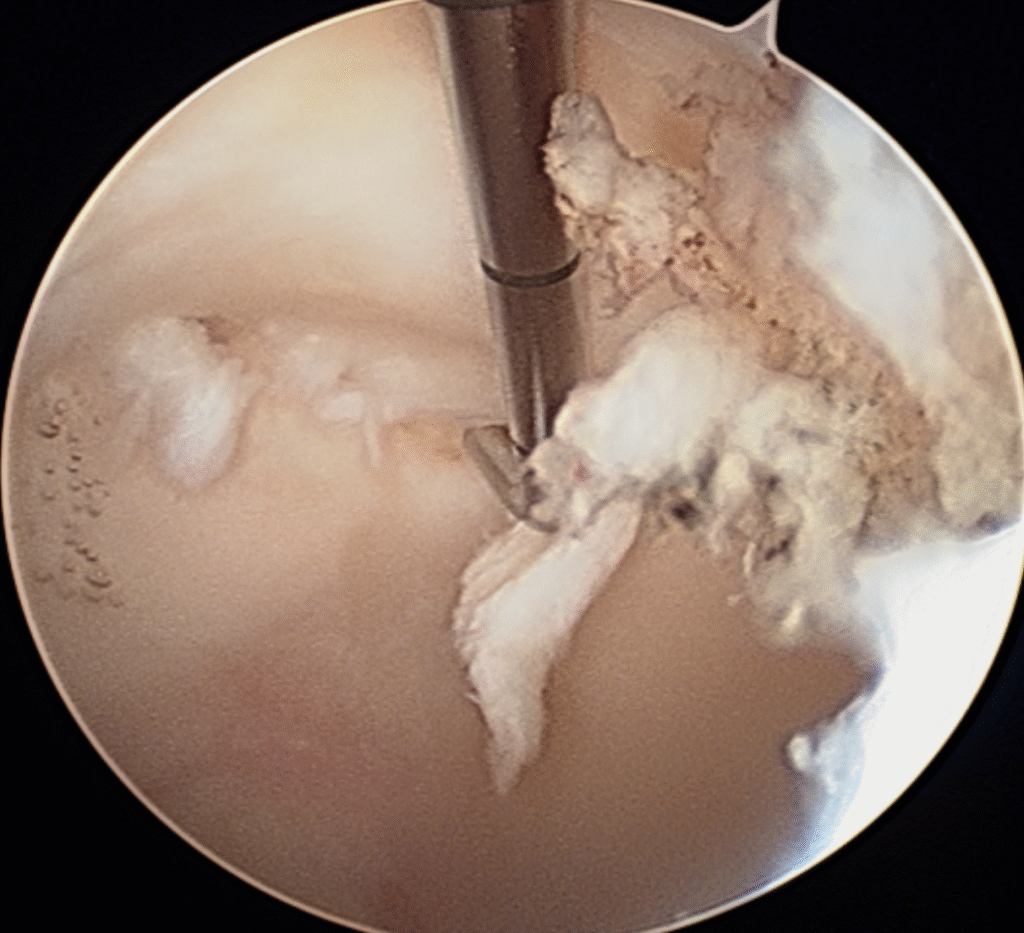

As lesões articulares da anca podem ser tratadas com cirurgia artroscópica. Os procedimentos artroscópicos são realizados com pequenas incisões (± 1 cm), utilizando uma pequena câmara e instrumentos finos para vizualizar e tratar as lesões no interior da articulação.

Na artroscopia é possível reparar ou limpar as lesões do labrum e algumas lesões da cartilagem articular, remover corpos livres intra articulares e regularizar algumas alterações ósseas presentes no conflito femuro-acetabular.

Atualmente a indicação mais frequente para a artroscopia da anca é o conflito femuro-acetabular. É uma técnica pouco invasiva e segura mas apresenta uma curva de aprendizagem considerável